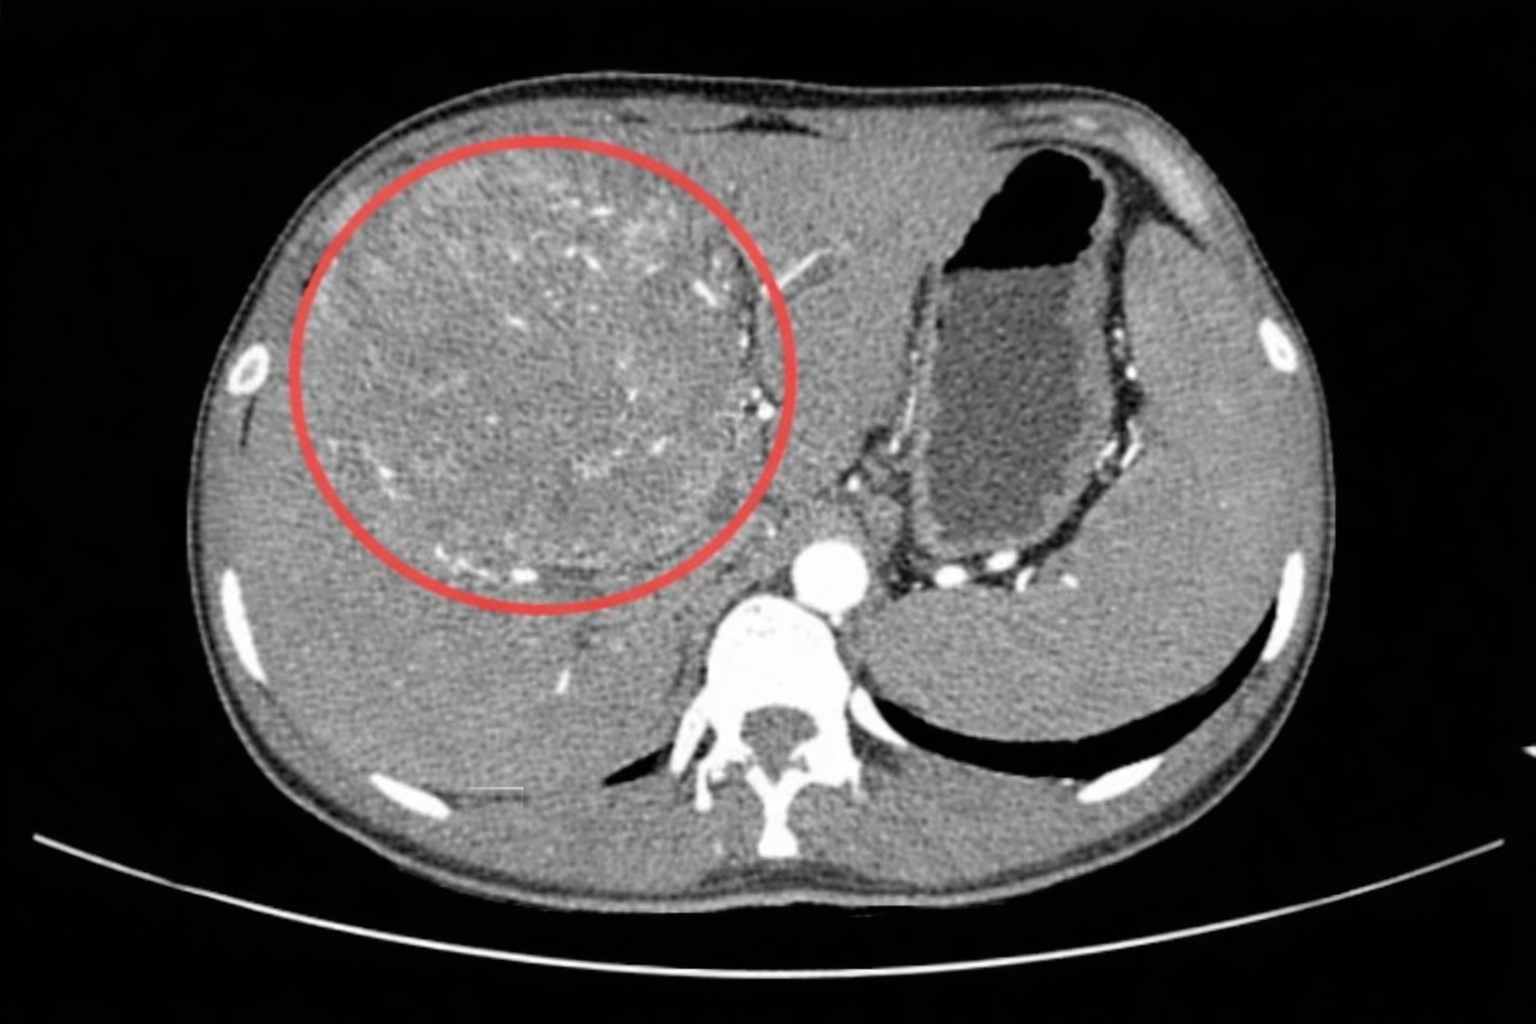

เรื่องราวที่สร้างความตกตะลึงให้กับวงการแพทย์และคนรุ่นใหม่เกิดขึ้นที่ โรงพยาบาลศูนย์อ่าวปินไห่ (Binhai Bay Central Hospital) เมืองตงกวน ประเทศจีน เมื่อทีมแพทย์ได้รับตัวผู้ป่วยชายวัยเพียง 25 ปี ที่มาด้วยอาการอ่อนเพลียเรื้อรังและท้องอืดอย่างรุนแรง แต่ผลการตรวจเอกซเรย์คอมพิวเตอร์ (CT scan) กลับปรากฏข้อความที่น่าสะเทือนใจว่า "พบเนื้องอกในตับขนาดใหญ่" พร้อมคำวินิจฉัยว่าเป็น มะเร็งตับระยะสุดท้าย